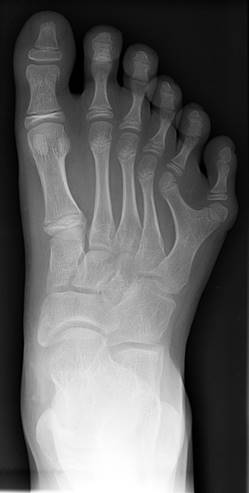

На трёх рисунках представлепредставлены фотографии детей разного возраста, и у всех имеются арактерные черты и признаки дизэмбриогенеза. Характерна мышечная гипотония в сочетании с разболтанностью суставов. Часто встречаются врождённый порок сердца, клинодактилия, характерные изменения дерматоглифики (четырёхпальцевая, или «обезьянья», складка на ладони — рис. 2.4, две кожные складки вместо трёх на мизинце, высокое положение трирадиуса и др.). Пороки ЖКТ наблюдаются редко. Частота какого-либо симптома в 100% случаев, кроме низкого роста, не отмечена.

Рис. 2.4 – Ладони взрослого мужчины с синдромом Дауна.